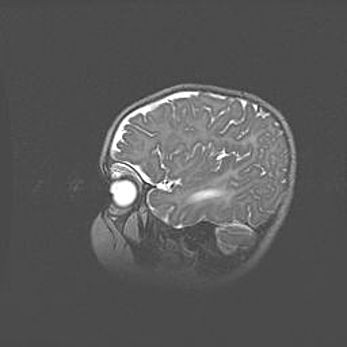

Мальформация Денди-Уокера. Киста задней черепной ямки.

Агенезия мозолистого тела.

Возраст: 2,5 месяца

Вес: 2420 г

Пол: женский

Окружность головы: 37 см

Срок гестации: 32 недели

Мальформация Денди—Уокера — редкий вид патологии ЦНС, представляющий собой врожденный порок развития каудального отдела ствола и червя мозжечка, ведущий к неполному раскрытию срединной (Мажанди) и латеральных (Лушка) апертур IV желудочка мозга. Для этогно синдрома характерна триада симптомов: гипотрофия червя мозжечка и/или полушарий мозжечка, кисты задней черепной ямки, гидроцефалия различной степени. В 70% случаев порок сочетается и с другими аномалиями головного мозга, в частности с агенезией мозолистого тела.